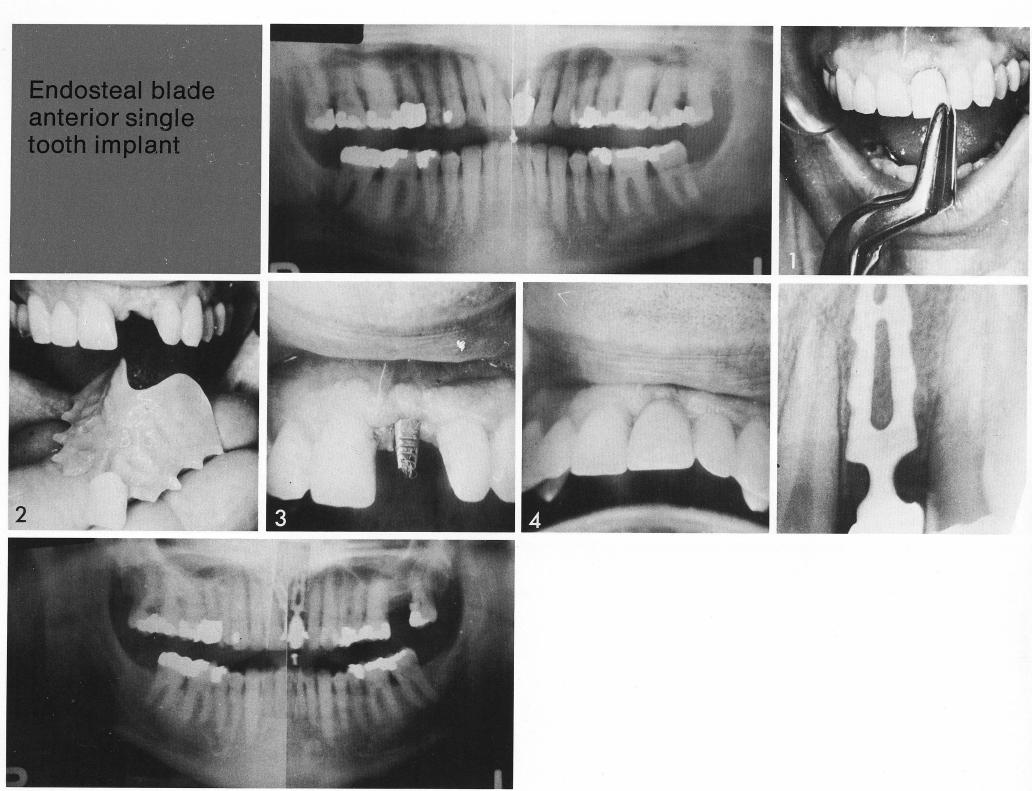

Endosteal blade

anterior single

tooth implant

The conventional appliance is clearly artificial (1), as well as bulky (2). The single-tooth implant (3) provides a stable abutment in good bone that looks much more natural than the removable appliance.

1 Single maxillary tooth implant provides a stable abutment in good bone